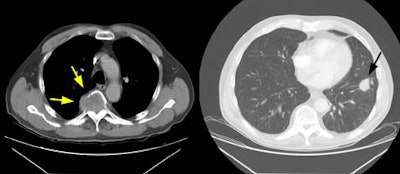

Example 1: The case below is an interesting example of a patient that presented with back pain and lower extremity weakness following a fall. A large soft tissue mass can be seen destroying the T5 vertebral body (yellow arrows). This proved to be metastatic non-small cell lung cancer from a 2.5 cm lesion (T1 by stage criteria) in the left lower lung (black arrow). There was no evidence of pathologic hilar or mediastinal adenopathy at CT. This patient is stage T1N0M1 (Stage IV).

Example 2: This is an interesting case of a patient with non-small-cell lung cancer who complained of right shoulder pain. The bone scan demonstrates a bone lesion in the proximal right humerus (blue arrow) consistent with a metastasis. The scan also revealed linear uptake of tracer along the distal femurs and tibias bilaterally (black arrows). Uptake in the forearms was more irregular. A coned down plain film of the distal left femur demonstrated a solid periosteal reaction (white arrows). The findings are consistent with hypertrophic osteoarthropathy- a paraneoplastic condition seen in association with bronchogenic carcinoma.

NOTE: Click directly on the image to enlarge.